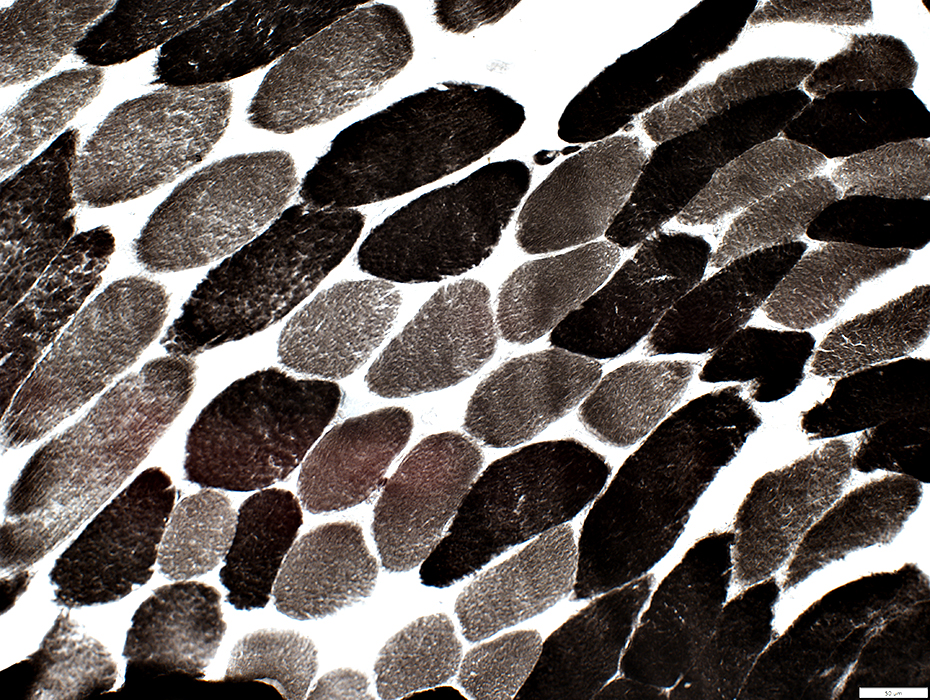

Succcinate Dehydrogenase (SDH)

Muscle fibers have increased staining

SDH stain